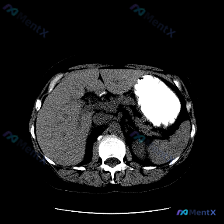

整理了一份很有启发性的CT读片分析,刚好踩中了临床思维里很经典的一个“陷阱”,分享出来大家一起讨论。 --- 先看原始预设与影像事实 这次的初始问题是「图像中的特异性异常是什么?脾脏病变」,但拿到CT影像仔细看下来,事实刚好相反: 核心影像表现整理 1. 脾脏(预设焦点): 形态正常,实质密度均匀,...